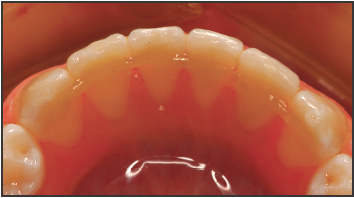

Fig. 3 Fiber completely covered by composite in finished retainer.